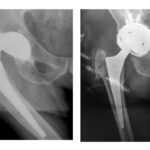

Στην εικόνα 1 επάνω αριστερά, ασθενής με φθορά στο “πλαστικό” της αρθροπλαστικής, χωρίς σημαντικά συμπτώματα. Συστήσαμε άμεση επέμβαση αντικατάστασης, συμβουλή που δεν ακολούθησε. Λίγους μήνες μετά, κάτω αριστερά, η πρόθεση της κοτύλης μετακινήθηκε εμφανώς πλέον και η αρθροπλαστική εξαρθρώθηκε. Αντιμετωπίστηκε (δεξιά) με επέμβαση αναθεώρησης της κοτύλης με τοποθέτηση οστικού μοσχεύματος και ειδικού  τύπου πρόθεση, με άριστο αποτέλεσμα.